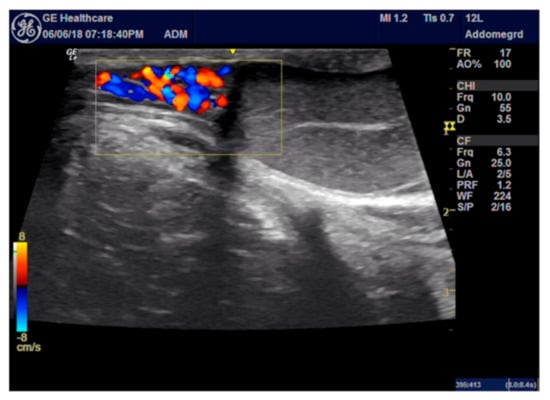

2.4. ROP Group Protocol